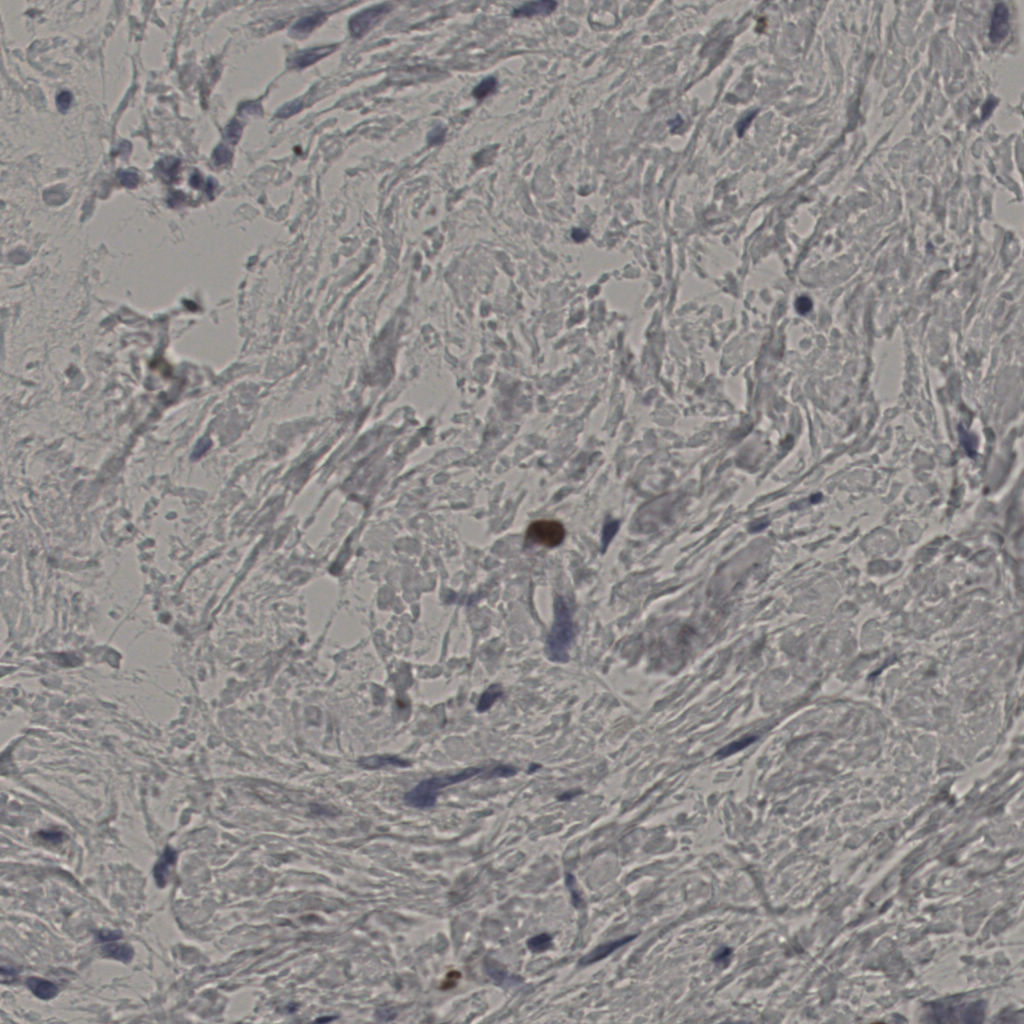

切片统计

总切片

2970

有效

554

已标记

554

有效率

19%